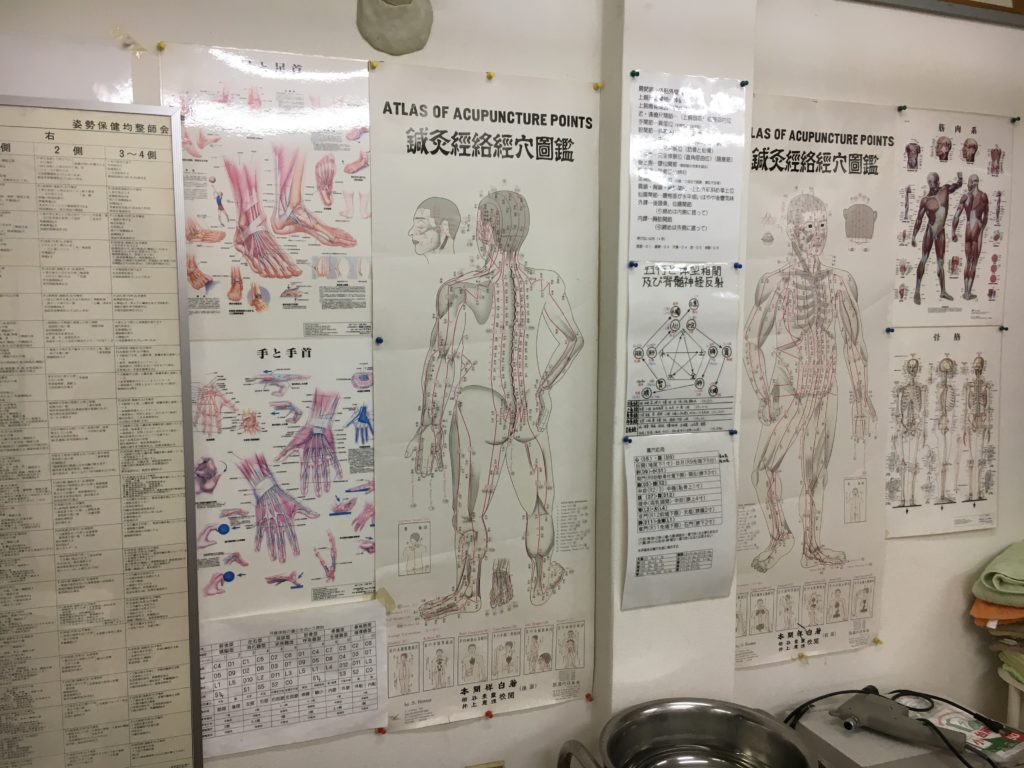

こんにちは。 整体知恵袋の たなかひろやす です。 今日は 「自分で緩めるローテーターカフ」を テーマにお話させていただきます。 身体均整法の創始者である亀井進師範は、 痛みの処方「募穴応用」の講義内で 「募穴は体の前面 […]

こんにちは。整体知恵袋のたなかひろやすです。今日は「遠隔で首を緩める方法」をテーマにお話させていただきます。ワタシが学んでいる身体均整法には脊髄神経過敏点と言うのがあります。これは、かかる場所を緩めると、そこに関連する椎 […]